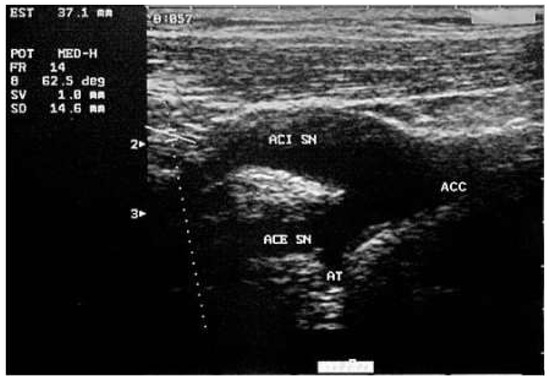

Carotid Ultrasonography in the Assessment of Cardiovascular Risk

by Aldo Pende, Nathan Artom, Giovanni Pistocchi, Livia Pisciotta and Franco Dallegri

Cardiovasc. Med. 2015, 18(2), 61; https://doi.org/10.4414/cvm.2015.00309 - 18 Feb 2015

Carotid ultrasound is one of the most accessible examinations in daily clinical practice for the evaluation of the arterial status. However, the clinical implications of the presence, the extension and the morphology of carotid damage are not entirely clear. Aim of this narrative review is to discuss the role of carotid ultrasound in the assessment of cardiovascular risk through the examination of the updated evidence in the literature. We describe the technical aspects of the procedure and the possible correlations between the imaging results and the assessment of the cardiovascular risk. Some insights about new, more sophisticated techniques for carotid evaluation, such as carotid three-dimensional and contrast-enhanced ultrasound, are also presented. Full article

Figure 1